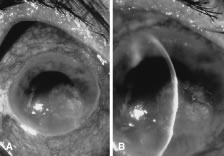

In the early stages of infection, filamentous fungi produce signs that are readily distinguishable from yeast or bacterial keratitis. The most distinctive sign is the presence of delicate, fine, feathery, opalescent, gray-white or yellow-white material in the anterior stroma, surrounded by scant cellular infiltrate or edema (Fig. 1). The epithelium may be intact. The overlying epithelium may be granular and the surface elevated and irregular in contour. Linear infiltrates typically extend into the adjacent stroma. Multiple discrete opacities may develop outside the perimeter of the principal focus of inflammation, either separated by clear stroma or linked by fine linear collections of inflammatory cells and material (Figs. 2 and 3). In the absence of inflammation in the adjacent stroma, branching hyphal fragments may be visualized by biomicroscopy (Figs. 4 and 5). Confocal microscopy may also detect hyphal elements within the stroma.28,29 Peripheral infection resembles noninfectious marginal infiltrative and ulcerative keratitis (Fig. 6). Multifocal keratitis may develop after contact lens wear or injury by multiple projectiles (Fig. 7). In the early stages, iritis is present and the intraocular pressure remains normal. Inappropriate, empirical therapy of fungal keratitis with topical fluoroquinolone or aminoglycoside antibiotics may suppress or eliminate the superficial elements but allow extension of the organisms into the stroma because these agents may possess selective antifungal activity.4,30,31

There is no distinguishing clinical sign by which to recognize the genus or species of the infectious filamentous fungus. F. solani is the most virulent organism and typically produces rapidly progressive infection characterized by epithelial and stromal ulceration, dense stromal necrosis, abundant cellular infiltrate, and edema in the adjacent stroma and hypopyon (Figs. 8 and 9). Delicate feathery components are transient. Individual hyphal fragments are rarely visualized. Infection by certain species of Aspergillus and Scedosporium (Figs. 10 and 11) resembles F. solani keratitis and progresses rapidly. Infection by less virulent organisms, such as Curvularia and Alternaria species, produces small, focal (less than 3-mm diameter) areas of nonnecrotizing stromal inflammation with delicate feathery borders (see Fig. 1 and Fig. 12). Macroscopic pigmentation may develop in keratitis caused by Alternaria, Curvularia, and other dematiaceous fungi (Fig. 13).4,11,14 The central component may progress to dense, opaque, gray-white suppuration in the deep stroma without enlargement in total area and may be accompanied by mild inflammation in the adjacent stroma. Iritis is minimal to moderate. Infection caused by other, relatively less virulent organisms resembles herpes simplex or noninfectious keratitis (Fig. 14).